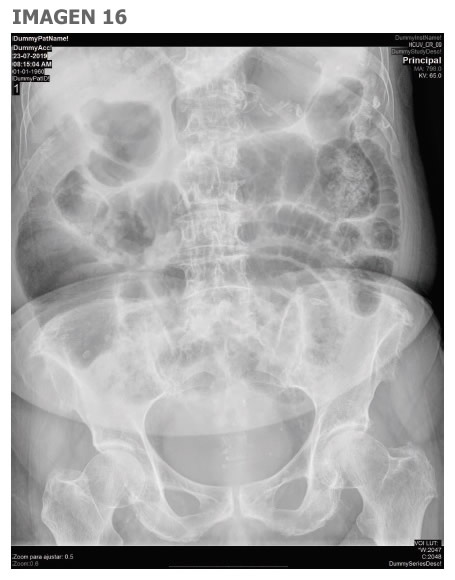

16. Pregunta vinculada a la imagen nº 16. Mujer de 94 años que acude a urgencias por dolor abdominal difuso e intenso de 12 horas de evolución y defensa abdominal. Entre sus antecedentes destaca cardiopatía isquémica crónica, fibrilación auricular persistente y enfermedad renal crónica. A raíz de los hallazgos de la radiografía de abdomen indique la actitud a seguir:

Imagen 16

Ecografía urgente como test de cribado inicial, si es normal no son necesarios más estudios radiológicos

Radiografía de abdomen en bipedestación o decúbito lateral izquierdo para valorar presencia de gas ectópico

TC abdominopélvico con contraste intravenoso con protocolo de angio-TC por sospecha de isquemia mesentérica

Arteriografía para descartar oclusión aguda de arteria mesentérica